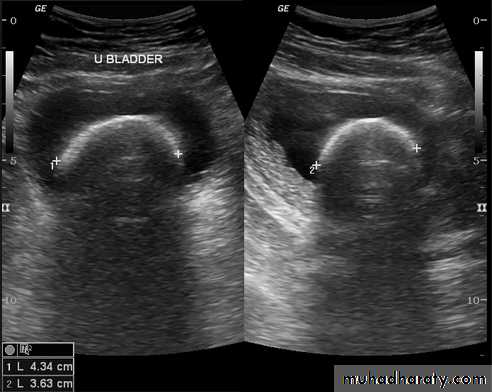

Urinary tract US

Renal ultrasound is a simple noninvasive examination .The kidney is bean shaped and has bright central echoes because of the fat surrounding the collecting system.

Ultrasound is typically ordered to exclude , stones , hydronephrosis or to evaluate renal size or suspected renal cysts .